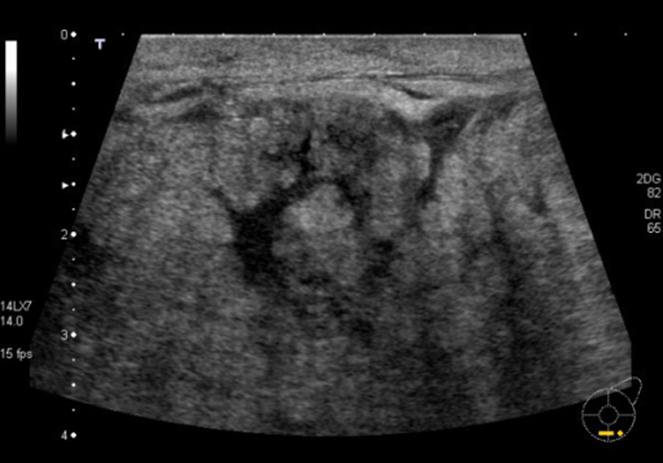

What are these images showing?

acute mastitis

What does chronic mastitis look like?

glandular tissue involvement

-mixed and diffuse echo pattern

-nipple discharge

-retracted/inverted nipple

Chronic Mastitis has what appearance on ultrasound?

heterogeneous